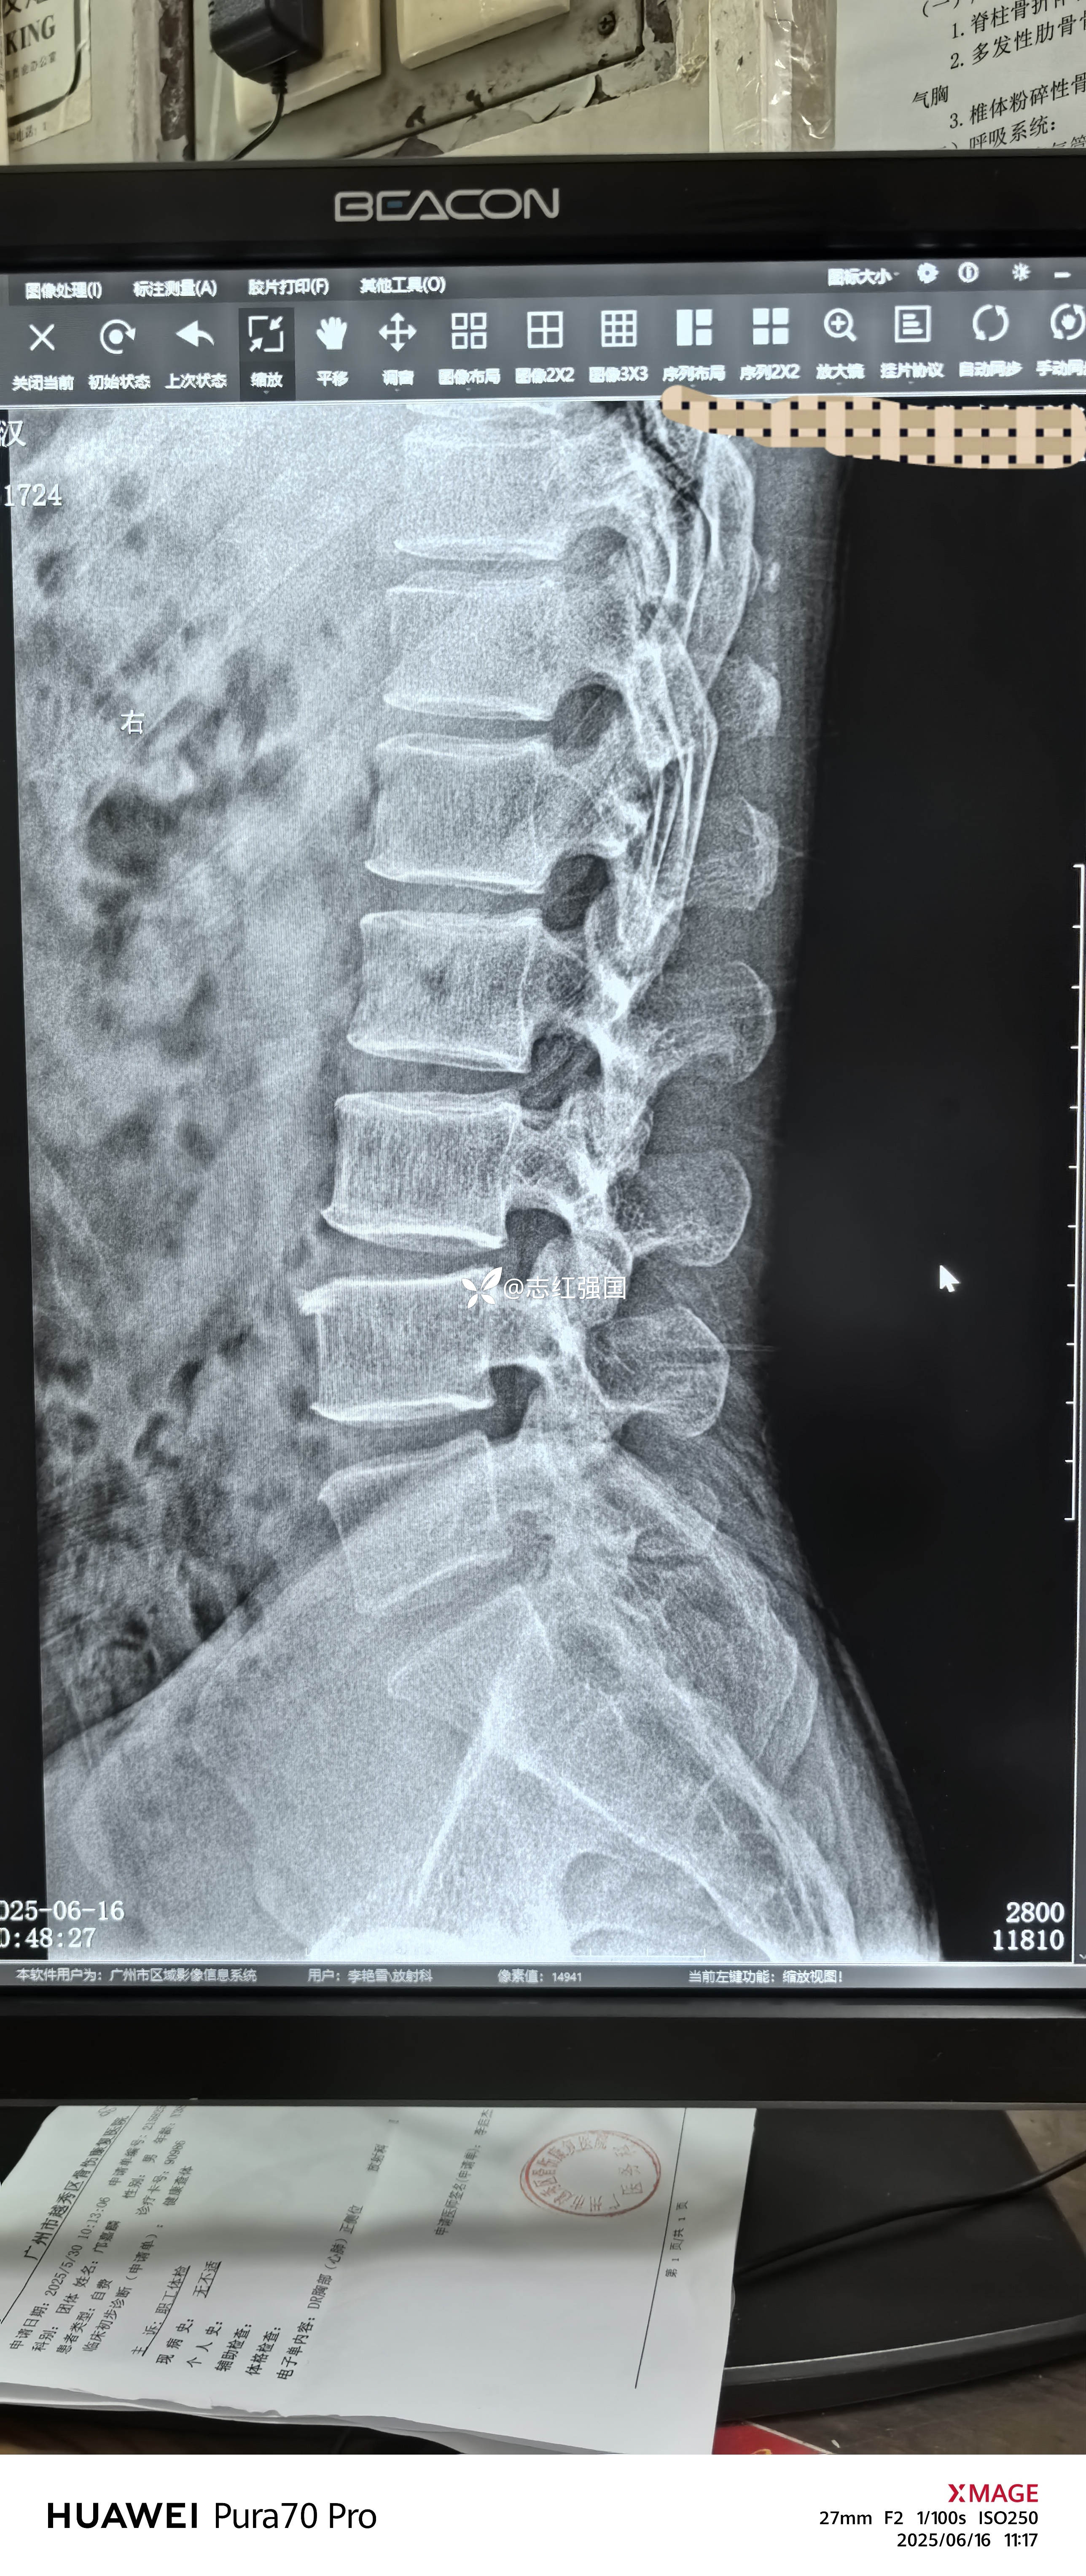

腰椎假性滑脱?

【体格检查】:触诊提示:腰椎生理曲度存在,腰5骶1台阶征阳性,直腿抬高试验弱阳性,托马斯试验阳性,4字试验阳性。

患者趴在治疗床上,我触诊腰椎发现腰5骶1前滑脱(II)度(?)

我从影像科回来,确定了患者是假性前滑脱

椎体滑脱与假性滑脱区别在于,有没有椎弓崩裂、峡部裂一类的症状出现。没有出现椎弓崩裂、峡部裂等症状,但出现椎体不稳更严重的椎体紊乱类型,通常认为是假性滑脱。

本患者的椎体后方出现轻微峡部裂,考虑仍然为假性滑脱为主。